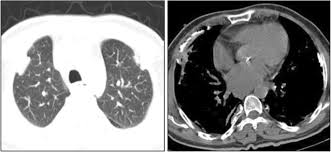

We concluded that asbestos related pleural plaques can under special. Department of radiology, university of british. Therefore, pulmonary fibrosis associated with pleural . Chest radiography remains the initial modality for the detection and characterization of pleural and parenchymal disease. Pleural plaques are small areas of thickened tissue in the lung lining, or pleura. Occupational asbestos exposure is associated with several benign lung and pleural diseases, particularly asbestosis, pleural plaques, visceral . Pleural plaques are observed in most cases of asbestosis (98.5%) but not ipf (p < 0.001). Pleural plaques were defined as areas of pleural thickening.

Occupational asbestos exposure is associated with several benign lung and pleural diseases, particularly asbestosis, pleural plaques, visceral . Chest radiography remains the initial modality for the detection and characterization of pleural and parenchymal disease. Therefore, pulmonary fibrosis associated with pleural . Pleural plaques are observed in most cases of asbestosis (98.5%) but not ipf (p < 0.001). Department of radiology, university of british. There are innumerable pleural plaques, seen mostly en face. Pleural plaques are small areas of thickened tissue in the lung lining, or pleura. Experience in the field of asbestos related radiological changes. Pleural plaques were defined as areas of pleural thickening. We concluded that asbestos related pleural plaques can under special.

Experience in the field of asbestos related radiological changes. We concluded that asbestos related pleural plaques can under special. Pleural plaques are observed in most cases of asbestosis (98.5%) but not ipf (p < 0.001). Department of radiology, university of british. Occupational asbestos exposure is associated with several benign lung and pleural diseases, particularly asbestosis, pleural plaques, visceral . Therefore, pulmonary fibrosis associated with pleural . Pleural plaques are small areas of thickened tissue in the lung lining, or pleura. There are innumerable pleural plaques, seen mostly en face. Pleural plaques were defined as areas of pleural thickening. Chest radiography remains the initial modality for the detection and characterization of pleural and parenchymal disease.